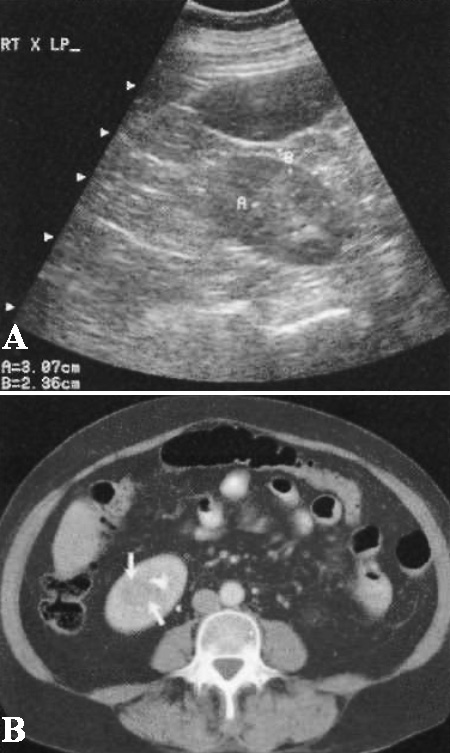

Очаговые зоны инфекционного процесса могут быть гипо- или гиперэхогенными, а также могут визуализироваться как объемные образования (фото 7)

Фото 7. Пиелонефрит. Ультразвуковое изображение правого нижнего полюса, на котором визуализируется гиперэхогенное объемное образование, размером 3 см, которое соответствует очагу пониженной плотности на КТ с усилением – картина очагового пиелонефрита